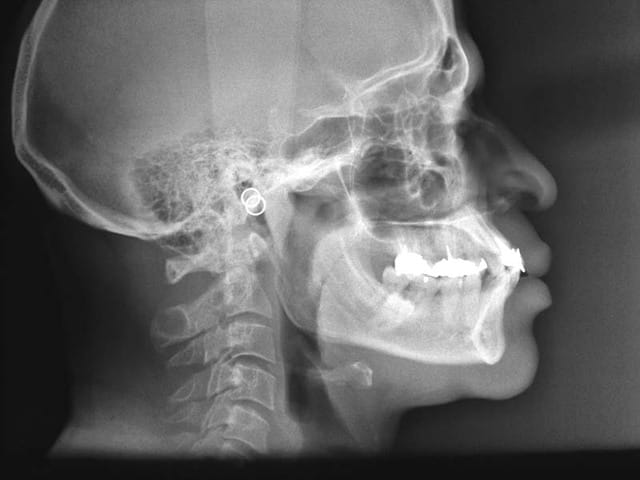

Pour ce qui est des incisives, au vu de la tele de profil je dirais que c'est la langue qui pousse.

Il deglutit comment le monsieur?